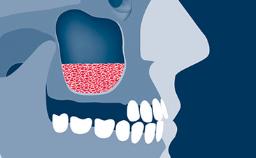

Sinus floor elevation using either the lateral window or transcrestal approach is a predictable surgical procedure with proven success, low complication rates, and high survival rates.

- intraoperative complications of lateral window sinus floor elevation

- postoperative complications of sinus floor elevation